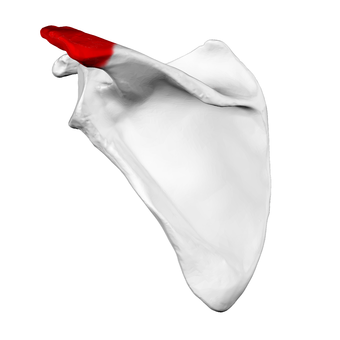

عظم الكتف الأيسر. صورة أمامية. يظهر الأخرم باللون الأحمر.